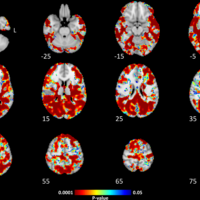

Vascular Cognitive Impairment (VCI) is a condition where the function of the brain is affected by diseases of the blood vessels, leading to problems with memory and thinking. It is the second most common cause of dementia, after Alzheimer’s disease.

We are a group of doctors, nurses, students, and research assistants who are looking to discover better ways to diagnose, prevent, and treat the conditions that cause vascular cognitive impairment, including treatment and prevention of stroke.